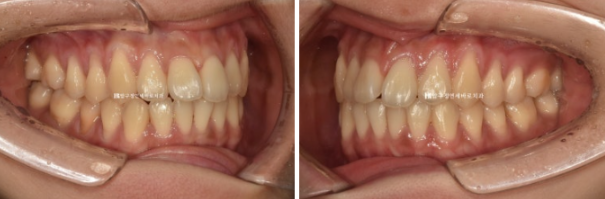

치료 전 - 치료 후 비교 사진입니다.

초진 24.02 이며 치료 종료는 24.07입니다.

24.02~24.07

좋은 교합은 유지가 되었고

토끼이빨은 정상 배열을 찾앗습니다.

깔끔해진 미소를 가지게 되었습니다.